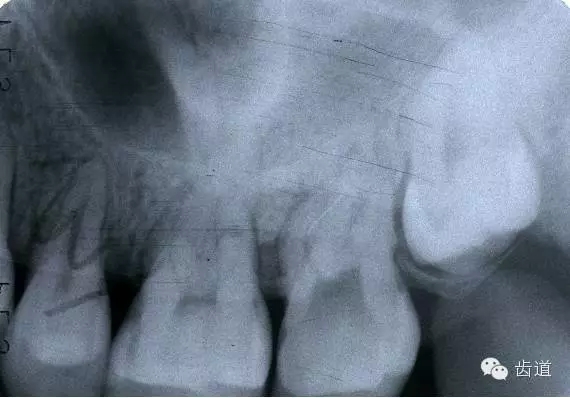

左下6底穿

左上6底穿